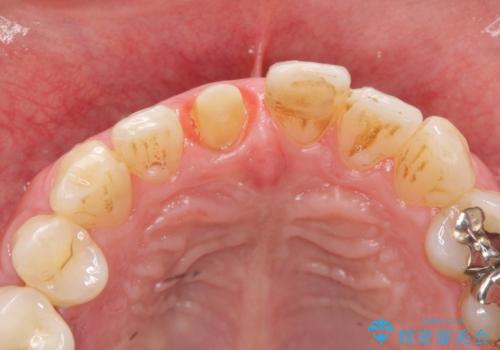

セラミッククラウン製作を行い審美性の改善を計画します。

- 15.4万円(仮歯・ファイバーコア・ジルコニアクラウン)費用は治療当時の料金となります

周囲の歯の色調に合わせた、自然なセラミック治療を行うことができましt。